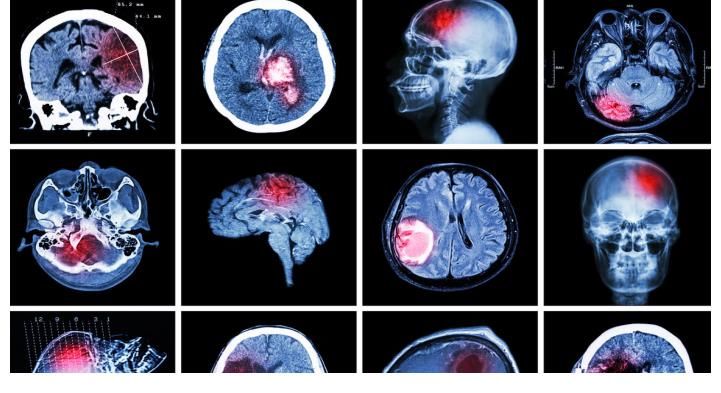

男子在抢救的过程中,脑部显示有大面积的出血,病情极为严重,必须马上动手术,可令人遗憾的是电击疗法、心脏按压、呼吸辅助能用的全给用上了,经过1个多小时的征战,患者最终还是没能挺过去。

三、诱发脑出血、冠心病等

擅自停药可能会使血压在短期内出现巨大波动,这时候如果没有及时的加以控制,就会大大增加脑出血、冠心病的风险,上文中张伟就是因为擅自停药引发的脑出血而与世长辞。